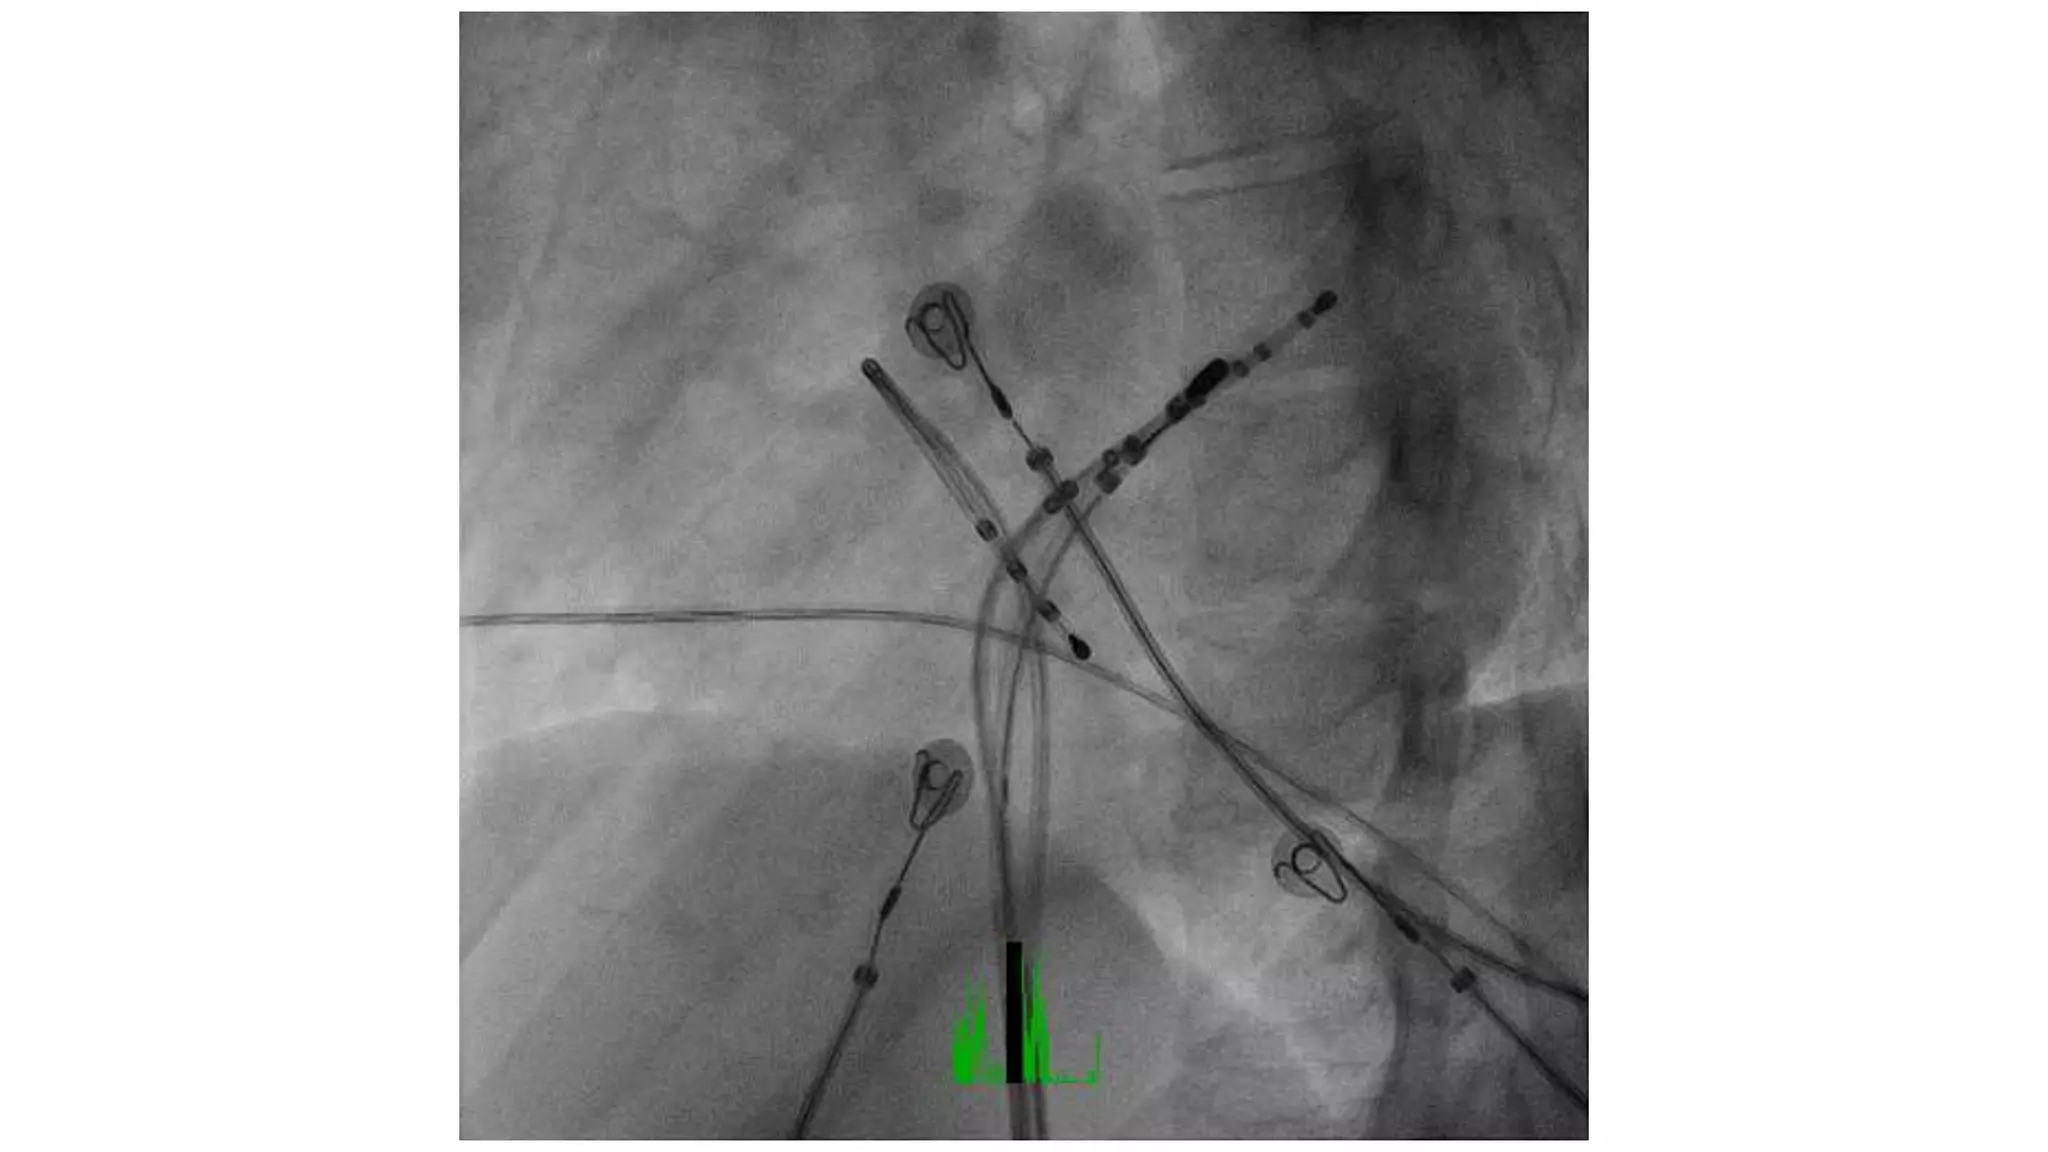

An electrophysiologic study involves inserting electrode catheters into the heart to record electrical activity and induce arrhythmias. The document discusses: 1. The procedure involves placing catheters in the heart to record electrograms from the atria, His bundle, ventricles and coronary sinus. 2. The aims are diagnostic to evaluate arrhythmias and bradycardias, and therapeutic for ablation of arrhythmias. 3. Key measurements taken include intervals between P waves, His bundle activation and QRS complex to identify conduction abnormalities. 4. Tracings are analyzed to determine the rhythm, sequence of activation, effects of pacing, and identify arrhythmia mechanisms like accessory pathways